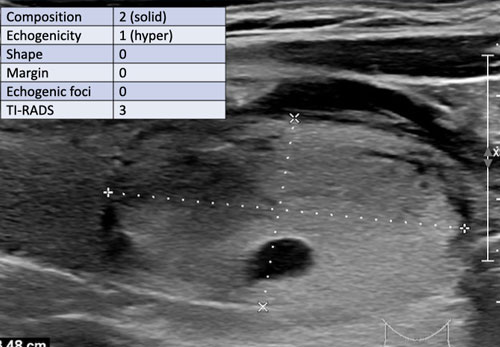

Trường hợp 2

Quan sát hình ảnh và xác định điểm TI-RADS.

Cuộn hình ảnh để xem điểm TI-RADS.